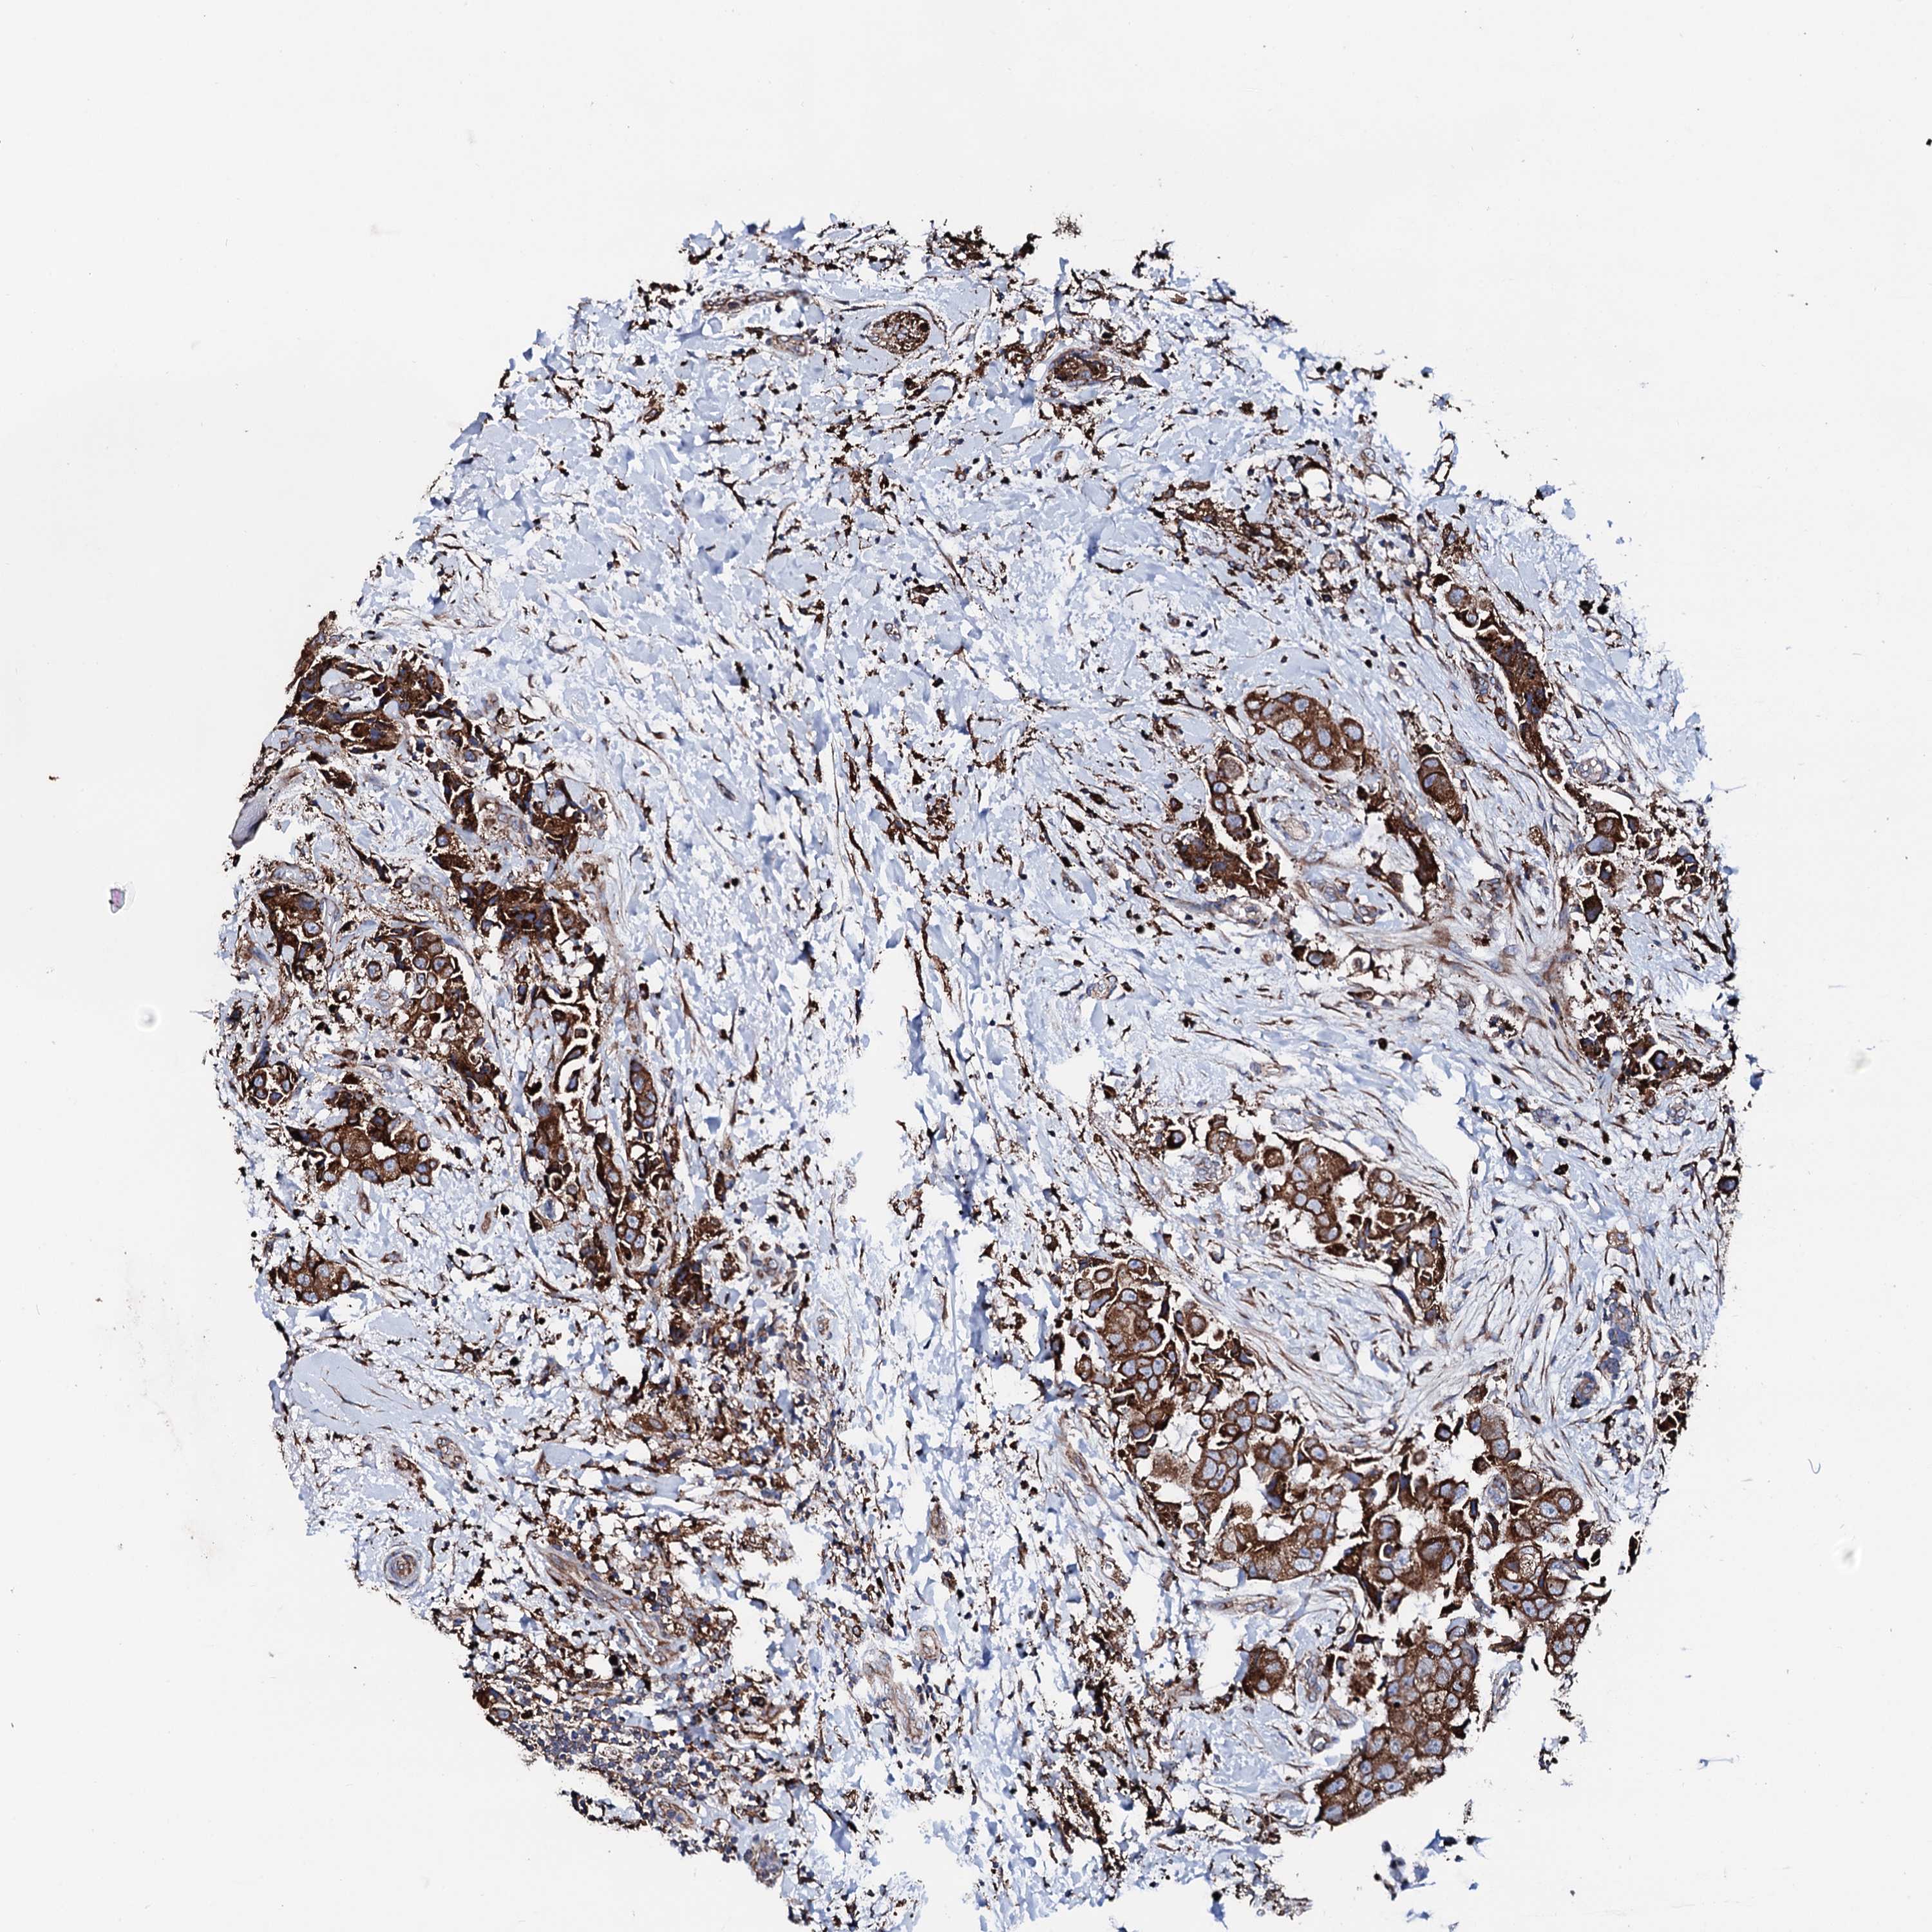

CANCER BREAST CANCER Show tissue menu

BRCA TCGA BRCA VALIDATION PROTEIN EXPRESSION